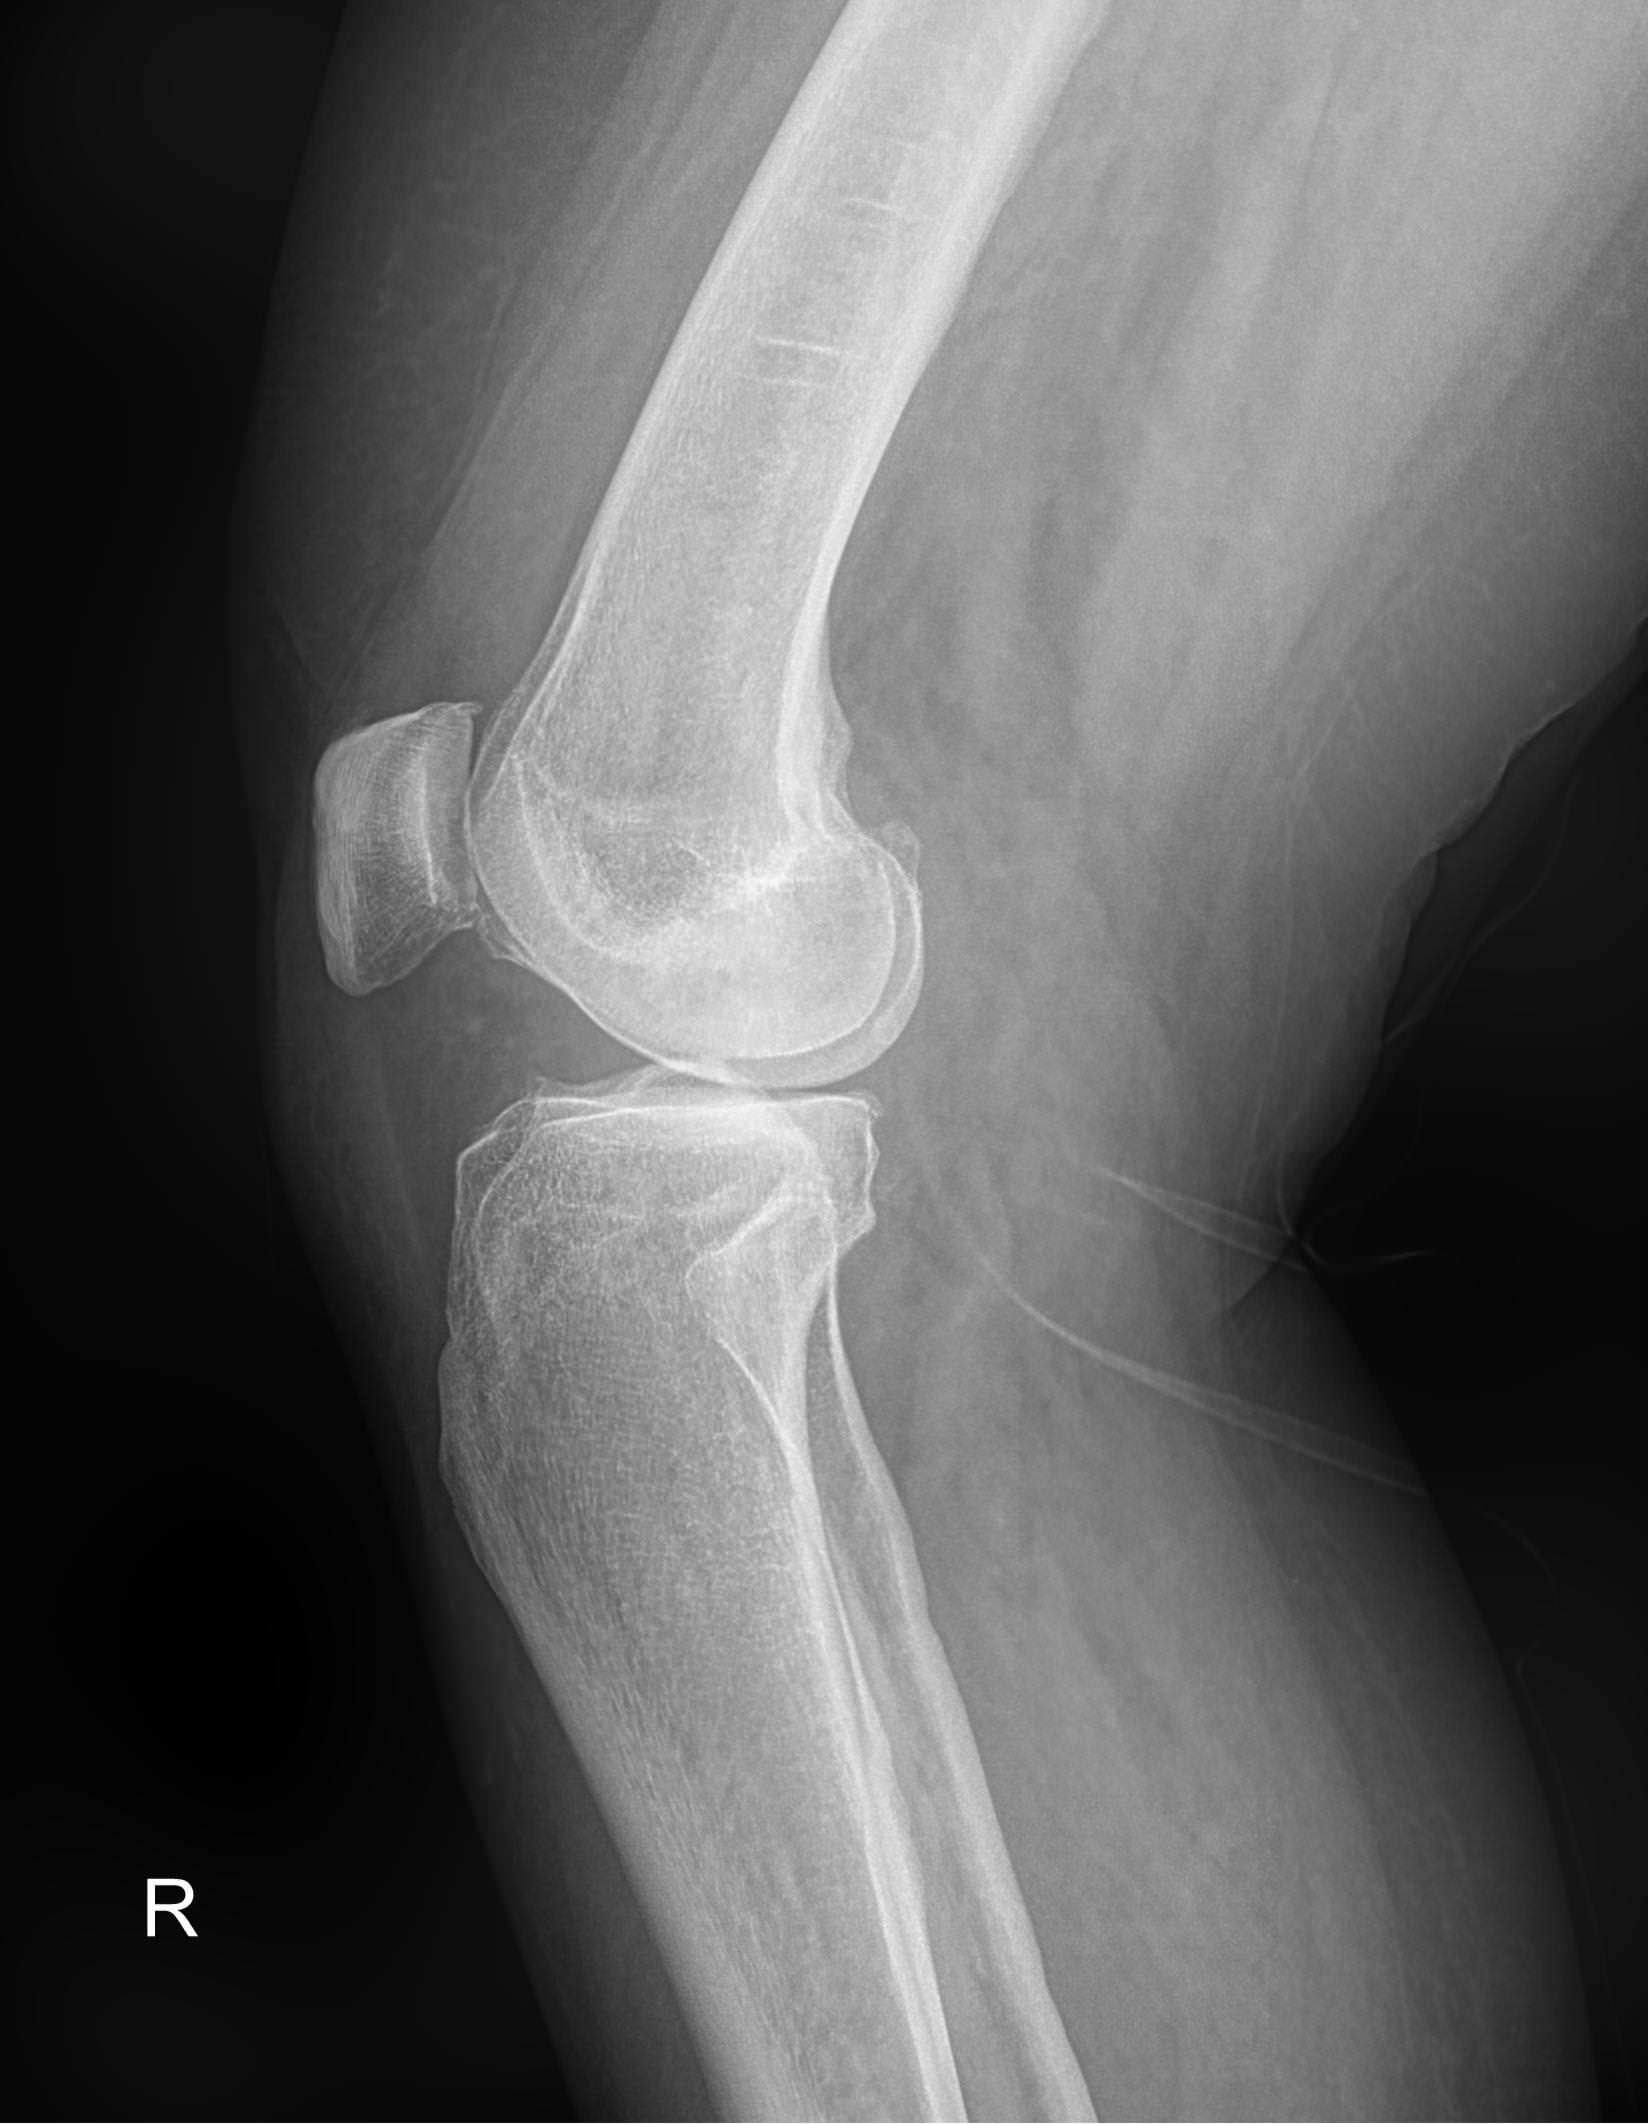

Рентген ― самый простой и быстрый метод диагностики поражения коленных суставов. Это неинвазивный и безболезненный , а также высокоинформативный способ увидеть внутреннее состояние колена. Современное рентгеновское оборудование использует минимально возможную дозу облучения. При этом на рентгенограмме отчетливо просматриваются части бедренной, малоберцовой и большеберцовой костей, надколенник, а также мягкие ткани вокруг них.

На рентгенограмме будут видны элементы сустава и патологические изменения в них:

• Суставная щель ― может быть расширена или сужена, причем неравномерно, иметь выпот, выросты, костные и хрящевые обломки;

• Соответствие друг другу суставных поверхностей ― естественное или вывих;

• Положение надколенника ― может быть неестественным;

• Состояние костной ткани: перелом, разрежение, уплотнение, размягчение, склерозирование;

• Мягкие ткани ― нормальные или отекшие, с инородными телами.